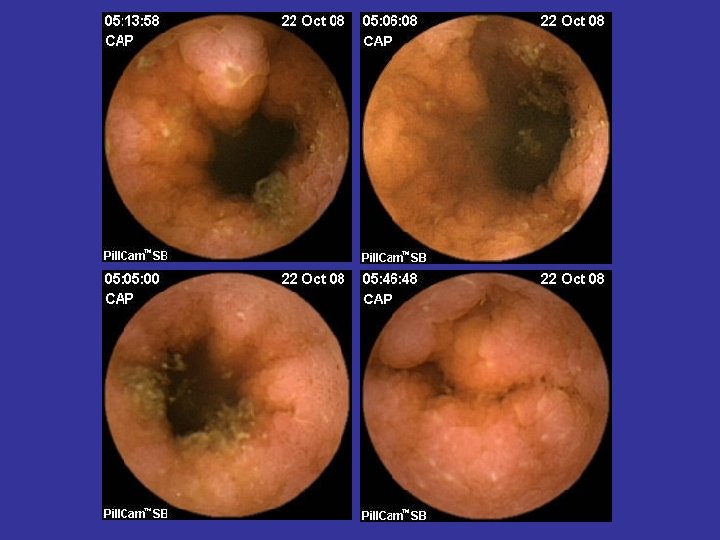

Tumorile intestinului subtire • Maligne (60%) – Adenocarcinoame – Limfoame – Tumori carcinoide – Metastaze (melanom) – Sarcoame • Benigne (40%) – Tumori stromale (GIST) – Adenoame – Hamartoame – Hemangioame